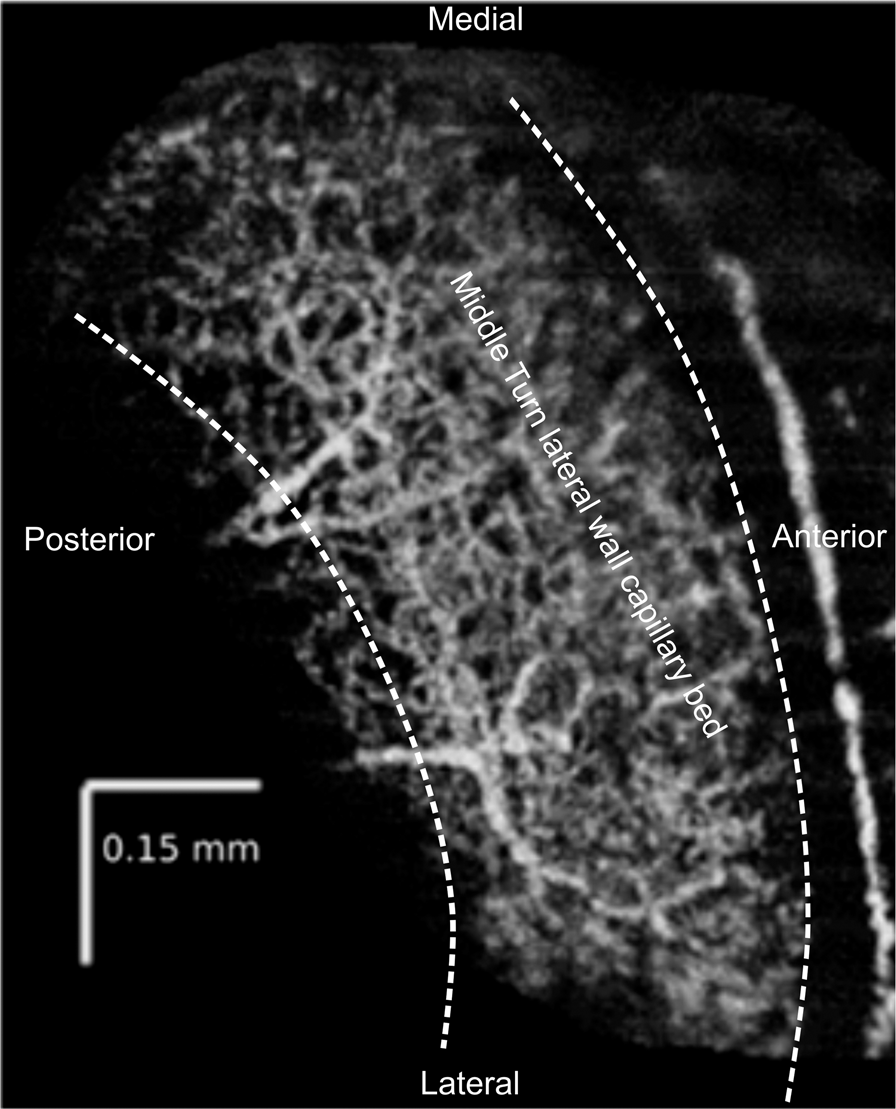

Figure 1

En face reconstruction of the ventral view of lateral wall blood flow in the middle turn of a murine left cochlea using OCTA. The middle turn organ of Corti (not visible) runs mediolaterally from low to high frequency along the cochlear spiral, between the two dashed lines, and includes the approximate location of a typical region of interest selection for flow analysis. This image is an average of 5 consecutive scans in the absence of sound.